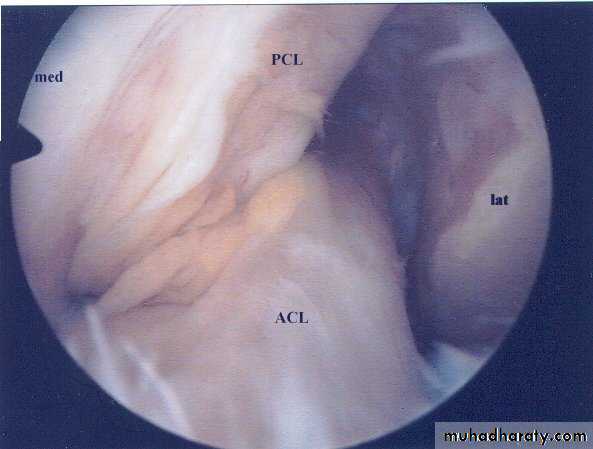

• Arthroscopy; it’s the best to give direct visualization of the inside of the joint to prove the diagnosis & exclude other possible injuries.

Arthroscopy can prove the diagnosis & show the site & type of the tear. Conservative treatment is only indicated for peripheral tears where the vascular meniscus may heal if the knee is rested for 3-4 weeks in POP or if the meniscus is sutured.Otherwise operative treatment is always indicated by arthroscopy, the aim is to excise the torn part of the meniscus only & leave the remaining intact part to avoid later degenerative changes of the knee.

Always remember the possible associated injuries as ACL tear, fractures or synovial damage and heamarthrosis.

Untreated ACL or collateral ligament tears may cause chronic joint instability with variable symptoms, functional disturbances & possible later osteoarthritis.Those patients needs good clinical & arthroscopic assessment, together with intensive course of physiotherapy & muscle strengthening exercises (including the quadriceps & hamstring groups) all to improve joint stability & function.